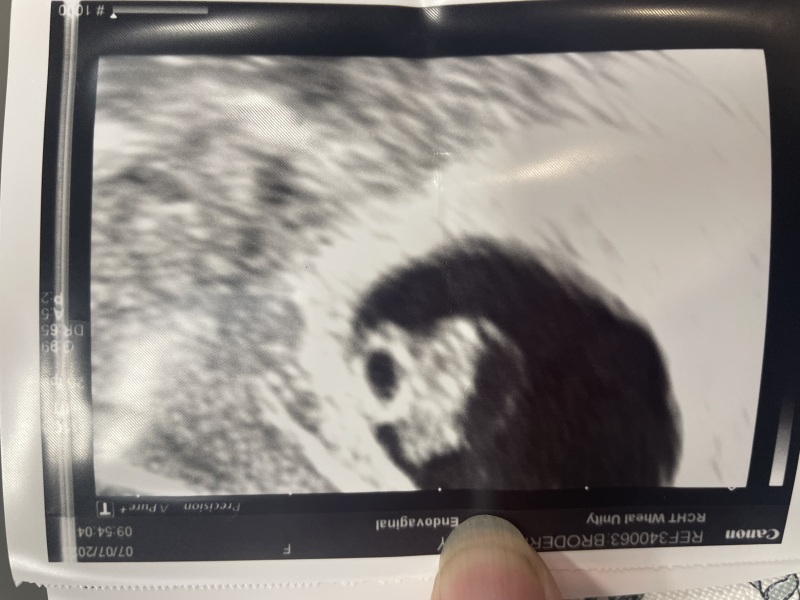

I had my 7 week scan yesterday and all is perfect!!! 🥰😳🥳 bub is measuring 9.2mm 😍😍 and has a strong heartbeat! I can’t believe it! It all still feels very surreal and I’m very guarded still, we all know too well how many things can go wrong! But I definitely feel more hopeful 🙏🏼❤️🥹